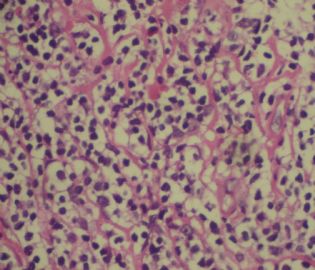

标本名称:  左前臂数个大小不等的皮下肿物。

既往有非何杰金淋巴瘤(滤泡性淋巴瘤)病史22个月。

• 左前臂数个大小不等的皮下肿物     淋巴瘤?图1

图1

病例不错。细胞胞浆透亮,间质血管丰富,图片不是很清晰,似乎有嗜酸粒细胞?

恶性,首先考虑T-NHL。IHC证实。

既往有NHL病史,图片不太清晰,细胞弥漫,胞浆透亮,首先考虑T细胞淋巴瘤。